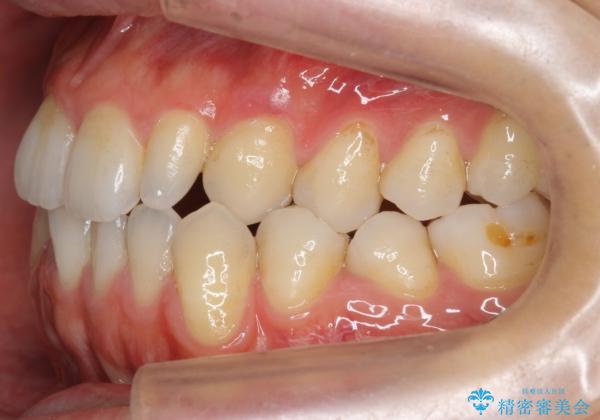

前歯の矮小歯 奥歯の反対咬合 をインビザラインで

- 上下の前歯が気になり来院。

左上2が矮小歯で小さく、また、左の奥歯が反対咬合になっていました。

左上2番はセラミッククラウンで反対側と同じ大きさにしました。

インビザラインでの臼歯の反対咬合の治療は難しいことが多いです。

今回は下の前歯を1本抜くことで、下の奥歯をしっかり内側に傾けて治療を行いました。